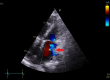

The diagnosis of atrial septal defect (ASD) may be delayed until adulthood or even later in life as it is a well-tolerated congenital heart disease. If patients are not examined and investigated well in childhood, the diagnosis may be delayed until later in adulthood when patients present with palpitations and sometimes dyspnea due to the right chambers dilatation from right ventricular volume overload. In this report, we present a case of a 50-year-old female patient with symptoms of heart failure and atrial fibrillation who was found to have dilated right cardiac chambers, dilated pulmonary artery, severe tricuspid regurgitation, pulmonary hypertension, and a pulmonary-to-systemic flow ratio (Qp/Qs) of more than 1.5 by transthoracic echocardiography and Doppler, indicating left to right shunt at the atrial level. However, transthoracic echocardiography could not visualize the defect, and two-dimensional (2D) transesophageal echocardiography was done in this patient and documented the presence of a sinus venosus ASD with an incomplete cor triatriatum dexter membrane; all four pulmonary veins were identified going to the left atrium. Since the presence of an incomplete cor triatriatum dexter membrane (despite causing no symptoms) makes the percutaneous closure of the sinus venosus ASD and the percutaneous repair of tricuspid regurgitation very difficult, we decided to advise surgical ASD closure and tricuspid valve repair for the patient.